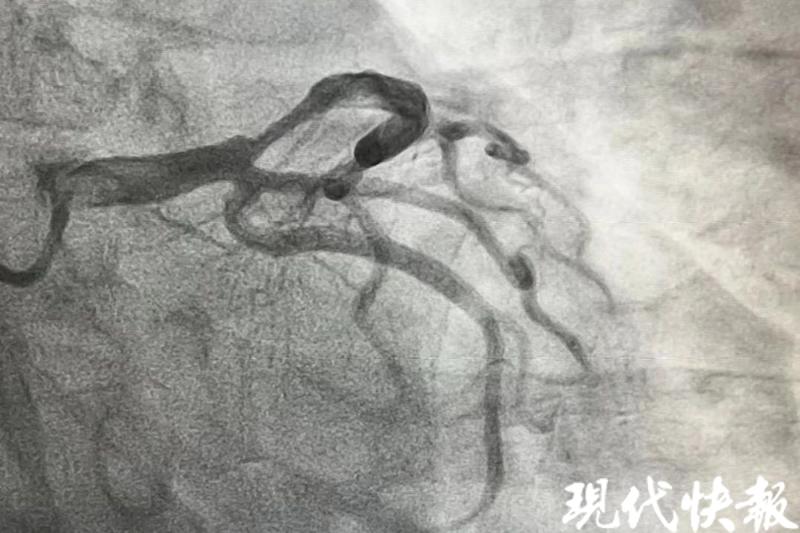

△患者心脏血管开通前

术中造影发现,张先生左前降支近段有85%至90%的狭窄,40分钟后,手术顺利结束,他安返病房。在医护人员的照护下,脱离生命危险。“患者才43岁,如果再迟点就医,有可能猝死,错失抢救的最佳时机。”曹松臻回忆。